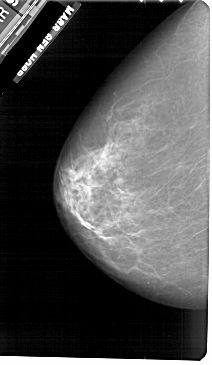

A_1908_1.RIGHT_CC

RIGHT_CC LINES 5491 PIXELS_PER_LINE 2971 BITS_PER_PIXEL 12 RESOLUTION 43.5 OVERLAY